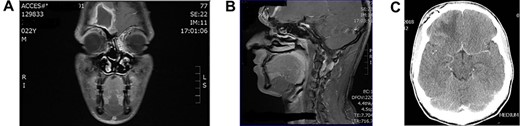

Young man referred as a case of frontal lobe abscess as a complication of untreated frontal sinusitis. The patient presented with fever, headache and changes in personality and mood. Coronal MRI brain (Fig. 4A) showed a large frontal lobe abscess and an inflamed frontal sinusitis as in Fig. 4B. the patient was managed with a combination of intravenous antibiotics, endoscopic frontal drainage and frontal craniotomy to drain the frontal abscess by the neurosurgery team. Patient tolerated the procedures well with no complications as shown in postoperative CT brain (Fig. 4C).

(A) Preoperation coronal MRI brain with large frontal lobe abscess, (B) preoperation sagittal MRI of frontal lobe abscess extending from inflamed frontal sinus and (C) post drainage CT brain showing complete resolution of the frontal abscess.